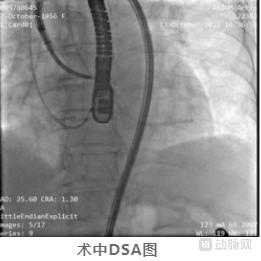

术中,方臻飞教授熟练操控DragonFire,根据术前确定的消融策略,连续对前间隔、中间隔基底部最为肥厚的心肌区域进行了精准的定位、穿刺,并进行对应能量范围的消融。

经导管经股动脉-心内膜路径心肌内射频消融术

DragonFire及其创新术式由诺沁医疗创新研发,联合中南大学湘雅二医院方臻飞教授团队共同研究。仅需在微创介入下经股动脉入路,经心内膜将消融针刺入室间隔肥厚心肌部位进行消融,进而减少室间隔心肌厚度,改善LVOT梗阻。可精确预测消融范围,无损伤外溢、传导术受损或术后低心排等传统无水酒精消融或外科手术常见严重并发症。